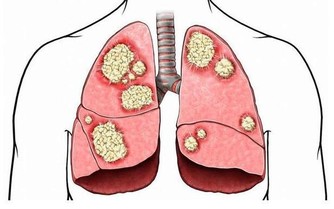

幾千年來,我們的祖先,飲食結構以糧食和蔬菜為主,所以我們的遺傳基因裡,本來就少有“吃肉基因”。現在生活好了,雞鴨魚,牛羊豬,天上飛的地上跑的水里遊的,無所不吃,少有“吃肉基因”的我們,吃下這些肉,自然各種疾病就跟著來了!

對於成年人來說,大魚大肉,營養過剩,從而引起各種慢性疾病,被稱為“富貴病”,這就不用我贅述了吧?